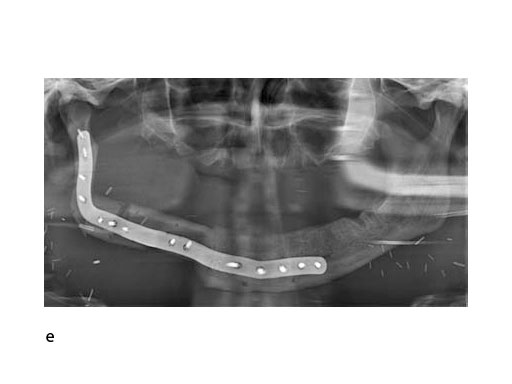

The innovative milled patient specific mandible reconstruction plates represent a paradigm shift in mandibular reconstruction, since these individualized plates complete the virtual work flow in computer assisted surgery. The optimal assembly of the bony segments is no longer compromised by manually bent plates causing secondary dislocation, since there is no leeway space in between the bone surfaces of the segments and the inner side of the plate.

With patient specific plates for mandibular reconstruction, the design of the bone flap now becomes the prevalent parameter because the plate is fabricated to exactly fit to the bony surfaces. This eventually means that the bony framework dictates the reconstruction, which allows for more conformity with the original anatomy, augmenting accuracy. To transfer the surgical plan into surgery, cutting guides and repositioning templates, both for resecting and contouring the bone flap, are prefabricated with Selective Laser Sintering (SLS) from polyamide. Patient specific plates are conclusively brought into alignment with native mandible and the neomandibular segments by using drill guides integrated in the resection or cutting templates. By using the drill guides, the plate holes can be targeted exactly to the holes drilled into the bone without a temporary in situ application of the reconstruction plate.

With the design of the bony framework being ready, the reconstruction plate is molded to the geometry of the outer surface of the neomandibular division. The plate profile (thickness 2.0 or 2.5 mm) is chosen and the plate screw hole pattern is customized. Relative to the osteotomy sites, the fibular segment configuration, and the adjacent native bone, the number, position, and angulation (up to 15) of the plate screw holes is specified with respect to overall stability. A defined screw hole position facilitates accessibility for screw insertion and avoids interference with nerves, tooth roots, osteotomy interfaces, and existing/future implants.

To conclude, it can be noted that the substractive milling process for the manufacturing of patient specific plates for mandibular reconstruction eliminates the need for manual back and forth bending. This improves the fatigue strength and allows for a lower overall plate profile in comparison to standard reconstruction plates.

A key advantage of patient specific plates for the mandible is the transfer of the bone work design into surgery without any compromise by insufficiently adapted plates that could lead to unwanted displacement, and in the extreme, to healing problems. A decisive requirement is to establish a complete digital workflow for the design and production of all necessary tools and models, to finally obtain an optimally fitting bony reconstruction stabilized by a patient specific plate.